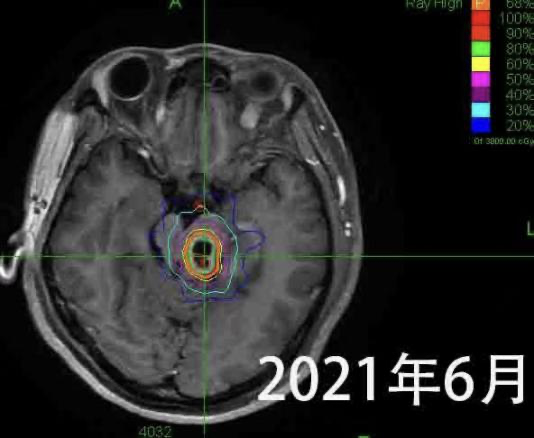

A female patient presented with a brainstem glioma, experiencing two months of weakness while walking and numbness in her right limbs. MRI revealed a tumor in the left brainstem, and pathology confirmed a brainstem glioma.

Dr. Wang Enmin developed a treatment plan combining CyberKnife with conventional radiotherapy for this challenging case. He explained: “We used five sessions of CyberKnife radiosurgery followed by 12–15 sessions of conventional radiotherapy. The goal was to escalate the dose inside the tumor using CyberKnife, while conventional radiotherapy covered potential tumor cells beyond the visible boundary.”

More than four years later, the patient remains in excellent condition, leading a normal life and working without restrictions. Dr. Wang emphasized the importance of regular MRI follow-ups. If small recurrences are detected, timely CyberKnife treatment can control progression. At her latest MRI check in August, the tumor had significantly shrunk.